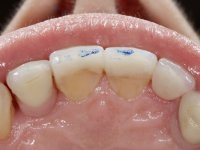

• Confeção e colagem de uma nova faceta feldspática para substituir a fraturada. A nova faceta deverá incluir maior área dentária inter-proximal distal do dente 2.1.

• Substituir a faceta do dente 1.2 por uma coroa total em cerâmica feldspática ou por uma, agora denominada, faceta 360.

O tratamento iniciou-se com a re -preparação do coto do espigão falso coto fundido, com o objetivo de colocar as linhas de acabamento cervical com uma localização intra-sulcular e simultaneamente confecionar uma coroa provisória adaptada. Com um tratamento ortodôntico muito simples, fechou-se o diastema entre os incisivos centrais superiores e estabilizou-se esta posição com um arame colocado na superfície palatina dos centrais, funcionando como contenção. Posteriormente procurou-se fazer uma tração ortodôntica lenta do dente 2.2 com o intuito de diminuir, ainda que muito ligeiramente a perda óssea vertical nessa zona. Finalizada a tração, foi feita a extração do dente 2.2 e a zona foi reabilitada provisoriamente com uma coroa de resina composta colada aos dentes adjacentes. Foi colocado um implante dentário na zona do dente 2.2 sendo novamente colada a coroa provisória em resina, reabilitando provisoriamente a paciente durante o período de osseointegração. No dente 1.3 foi feita uma gengivectomia com bisturi elétrico, com a intenção de subir o nível cervical do 1.3 conseguindo uma maior harmonia com o dente 2.3. Estabilizados os tecidos moles, foi feita uma impressão com a técnica de moldeira aberta, utilizando silicones de adição de consistência “putty” e “light”. A recolha da cor, tanto da componente dentária como dos tecidos moles foi feita pelo ceramista no consultório.  No laboratório as impressões foram passadas a gesso e deram origem a modelos de trabalho que foram devidamente analisados. Foi decidido confecionar um “abutment” metalo-cerâmico aparafusado sobre o implante. Este “abutment” foi fundido com uma liga nobre e posteriormente revestido a cerâmica coronária e gengival. Dada a inclinação do implante o aparafusamento condicionou de forma inevitável a saída do orifício do parafuso pela superfície vestibular. No sentido de esconder esta situação, o desenho do “abutment” já foi idealizado com a intenção de acomodar na superfície vestibular a colagem de uma faceta feldspática. Este “abutment” foi provado em boca e foram feitos ajustes no componente cerâmico gengival. A sua adaptação aos tecidos moles foi feita tanto de forma subtrativa, com broca, como de forma aditiva, acrescentando resina composta de tonalidade gengival. Este acrescento de resina seria orientador do ceramista na colocação final da cerâmica de tonalidade gengival. A coroa que reabilitaria o dente 1.3 foi cimentada nesta consulta de prova com cimento de ionómero de vidro reforçado com resina composta. Finalizado o trabalho em laboratório da faceta sobre o 1.2 e o “abutment” e a faceta para o implante este foi colado em boca, após a colocação do isolamento absoluto. O trabalho satisfez plenamente a paciente. Durante oito anos a paciente foi seguida regularmente, mostrando-se agradada com o tratamento efetuado, no entanto começou a mostrar interesse em intervir esteticamente nos incisivos centrais superiores. Decidida a segunda fase da nossa intervenção, foi feita a preparação dentária dos dentes 1.1 e 2.1 para a colocação de duas facetas feldspáticas. Particular cuidado foi tido na preparação inter-proximal distal junto ao “abutment” do implante. Foi preciso avaliar muito pormenorizadamente o eixo de inserção da faceta em relação ao “abutment”. As facetas feldspáticas foram confecionadas em laboratório e posteriormente coladas em boca após a colocação de isolamento absoluto. Um ano após, iniciamos a nossa terceira fase de tratamento, após a faceta colada no dente 2.1 ter fraturado. A preparação dentária foi feita sobre a faceta colada, procurando estender mais para palatino o interface inter-proximal distal. O objetivo seria passar para mais palatino do ponto de contacto o interface faceta-dente. O preparo dentário do dente 1.2 também foi muito reduzido, limitando-se a criar um eixo de inserção. Após confecionadas a coroa total e a faceta em laboratório foram coladas em boca. Primeiro foi colada a coroa utilizando-se um isolamento relativo com teflon, posteriormente foi colada a faceta após a colocação do isolamento absoluto. Na coroa utilizei este tipo de isolamento para evitar a utilização de grampos. Seria difícil de aplicar pela forma e dimensão do dente e agressivo para os tecidos moles. Após a colagem foi avaliada a integração oclusal do trabalho.